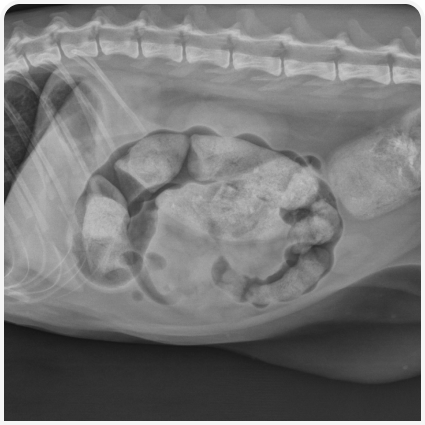

У кошек, страдающих запором, обычно удается транс­абдоминально пальпировать скопившийся в толстой кишке кал, но при тяжелом ожирении или в случае если животное проявляет беспокойство, это может оказаться непросто. Также могут появляться тошнота или признаки обезвоживания. Следует провести неврологическое обследование, включая пальпацию позвоночника, и офтальмологическое обследование, чтобы определить, является ли запор частью более обширного нервно-мышечного расстройства (например, вегетативной дисфункции, заболевания спинного мозга). Тщательное ректальное обследование под седацией или анестезией позволяет выявить каловые конкременты, объемные образования или инородные тела в заднем проходе, смещенные переломы таза, стриктуры прямой кишки, воспаление параанальных желез. Иногда у кошек в результате длительных фекальных тенезмов может образоваться грыжа промежности.

При необходимости проводят дополнительное обследование. Первой диагностической целью врача должно быть подтверждение запора и оценка его хронизации и тяжести, для чего обычно достаточно непосредственного обследования и рентгенографии, как описано выше. Учитывая, что идиопатический мегаколон и стеноз тазового канала составляют около 85% случаев (1), у большинства кошек при запорах обширное диагностическое обследование не требуется, но у отдельного пациента важно не пропустить поддающуюся лечению причину. Потенциальными показаниями для дальнейшего диагностического обследования служат неврологические нарушения (например, связанные с вегетативной дисфункцией), пальпируемые образования в брюшной полости или ректоанальной области, рентгенологически обнаруженные поражения брюшной полости / тазового канала, непропорциональная карликовость у молодых кошек (соответствует врожденному гипотиреозу) или другие признаки системного заболевания. К примерам иногда требующихся дополнительных тестов относятся определение гормонов щитовидной железы (т. е. общего Т4, свободного Т4, тиреотропного гормона) при подозрении на гипотиреоз, УЗИ органов брюшной полости при подозрении на объемные образования в стенке или вне просвета толстой кишки, рентгенография в поперечной плоскости при подозрении на заболевания позвоночника или объемные образования в полости таза, колоноскопия для выявления воспалительных поражений, ректоанальных стриктур или дивертикулов.